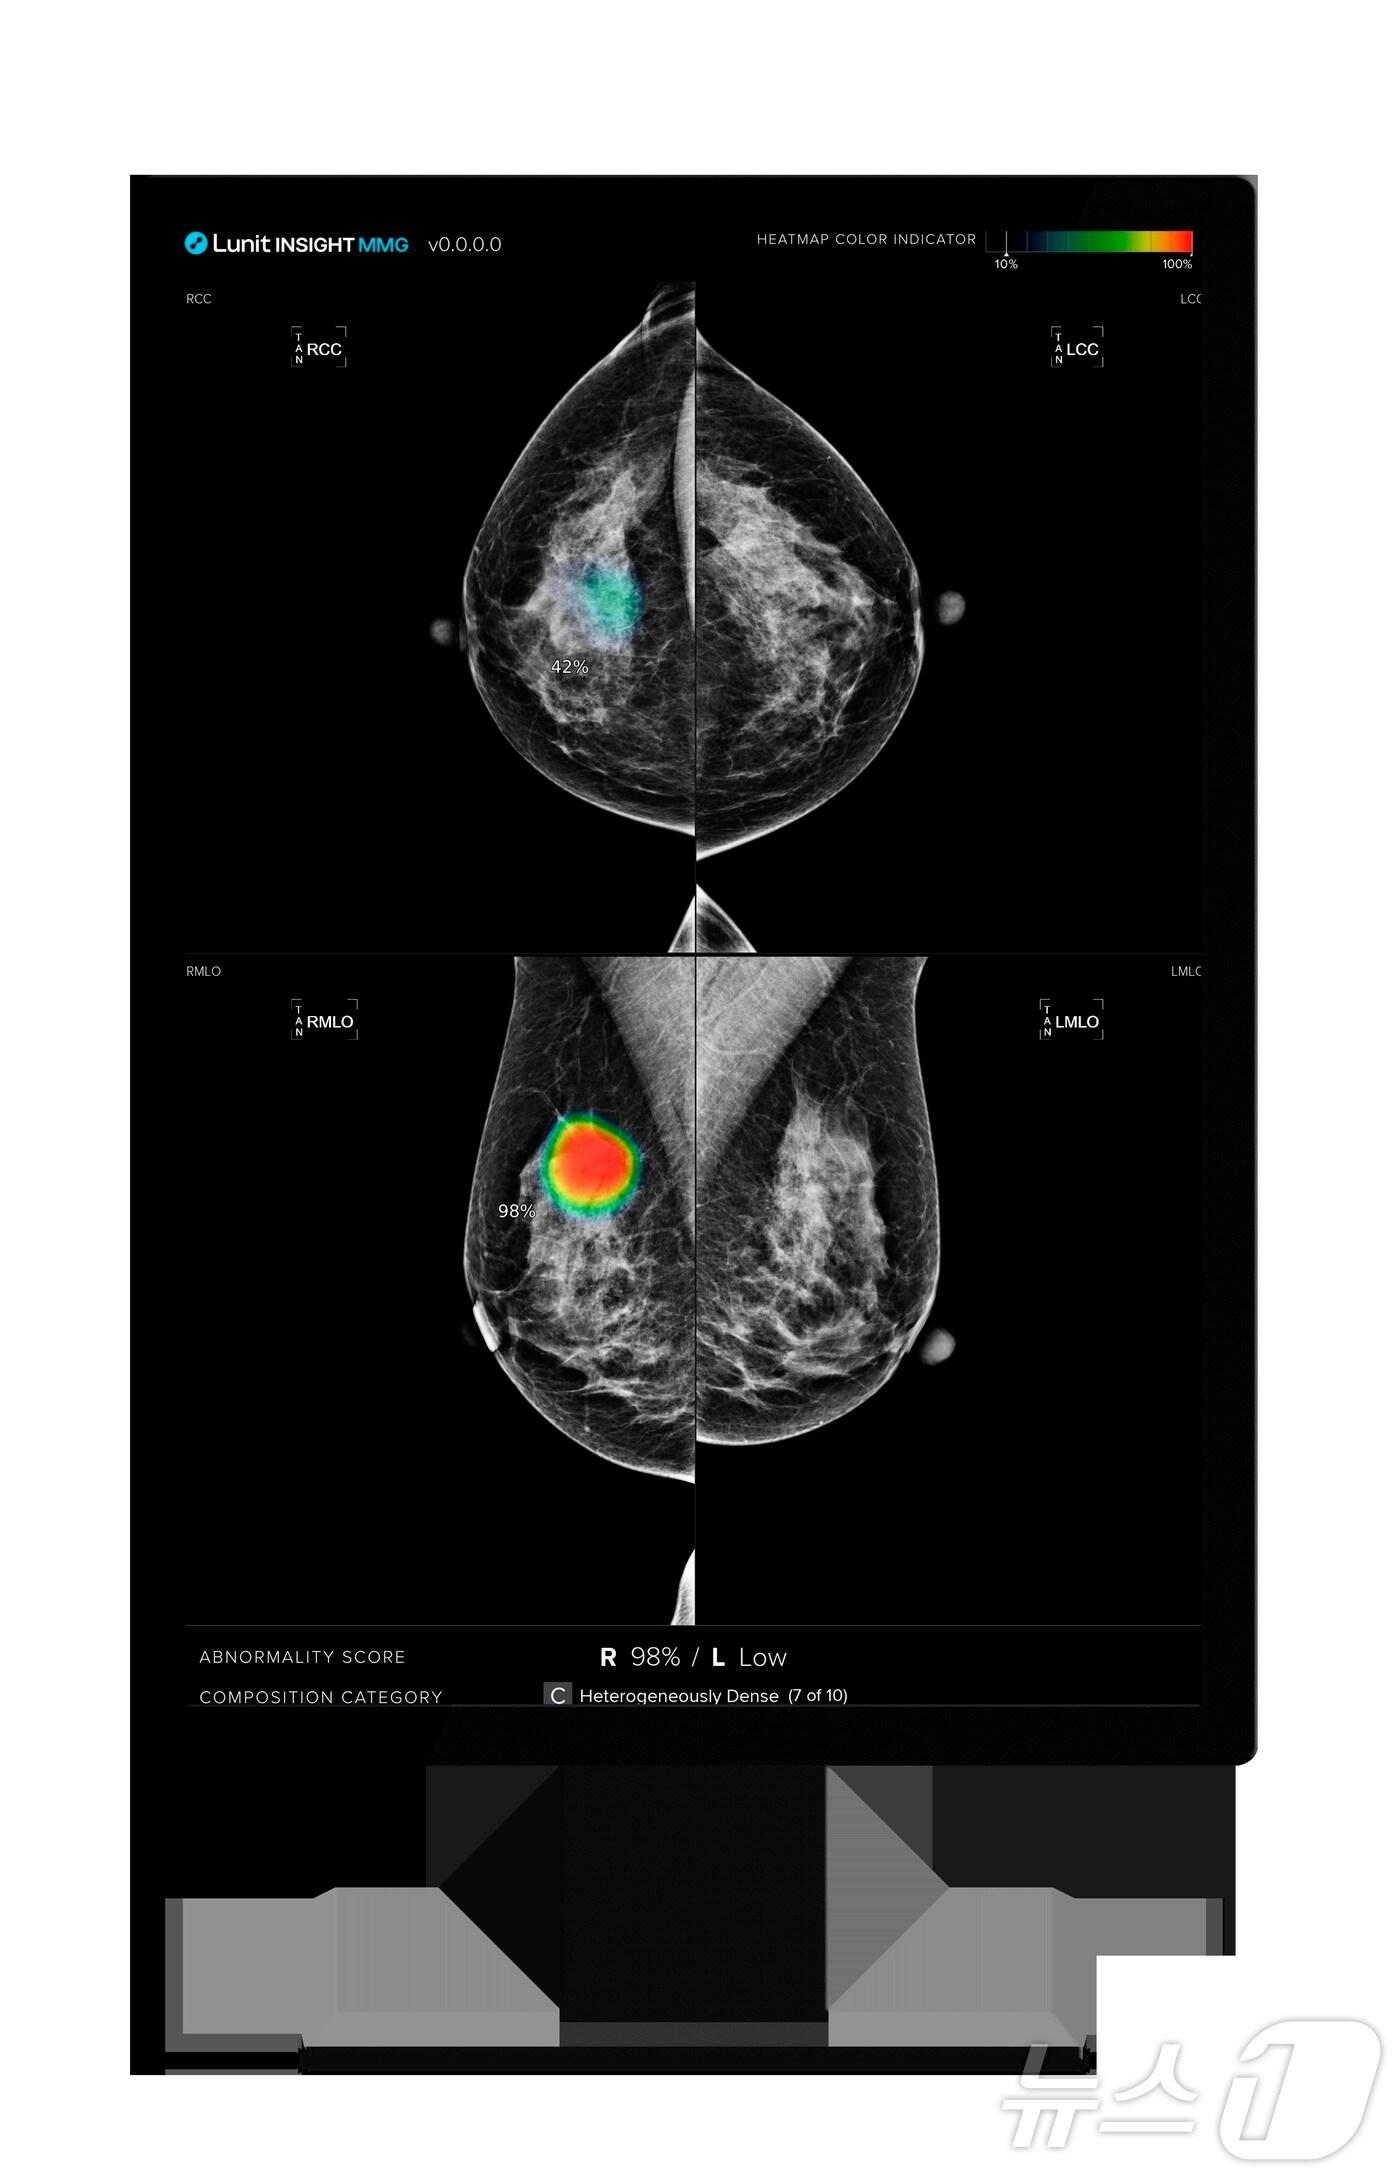

뉴사우스웨일스 주 정부 사업 참여…연간 3만 건 이상 활용"국가 암 검진 프로그램에 AI 솔루션 채택 최초 사례"루닛 인사이트 MMG 활용 모습.(루닛 제공)/뉴스1 ⓒ News1관련 키워드루닛루닛 인사이트AI 의료브레스트스크린황진중 기자 대웅 보툴리눔 美 파트너, 6년 연속 성장…"올해부터 흑자 지속"차바이오텍, 한화손보·생명서 1000억 규모 투자 유치…MOU 체결관련 기사루닛, 북미영상의학회서 유방암 검진 실효성 입증…”글로벌 표준”루닛, 美 의료기관에 AI 파운데이션 모델 공급…해외 계약 물꼬'볼파라 통합 마무리' 루닛, 내후년 흑자전환 자신…"수익 개선 궤도"루닛, 美학회서 AI 의료 솔루션 연구초록 14편 발표루닛, 美 진단시장 1위 랩콥과 전략적 협업…공동 연구개발 확대